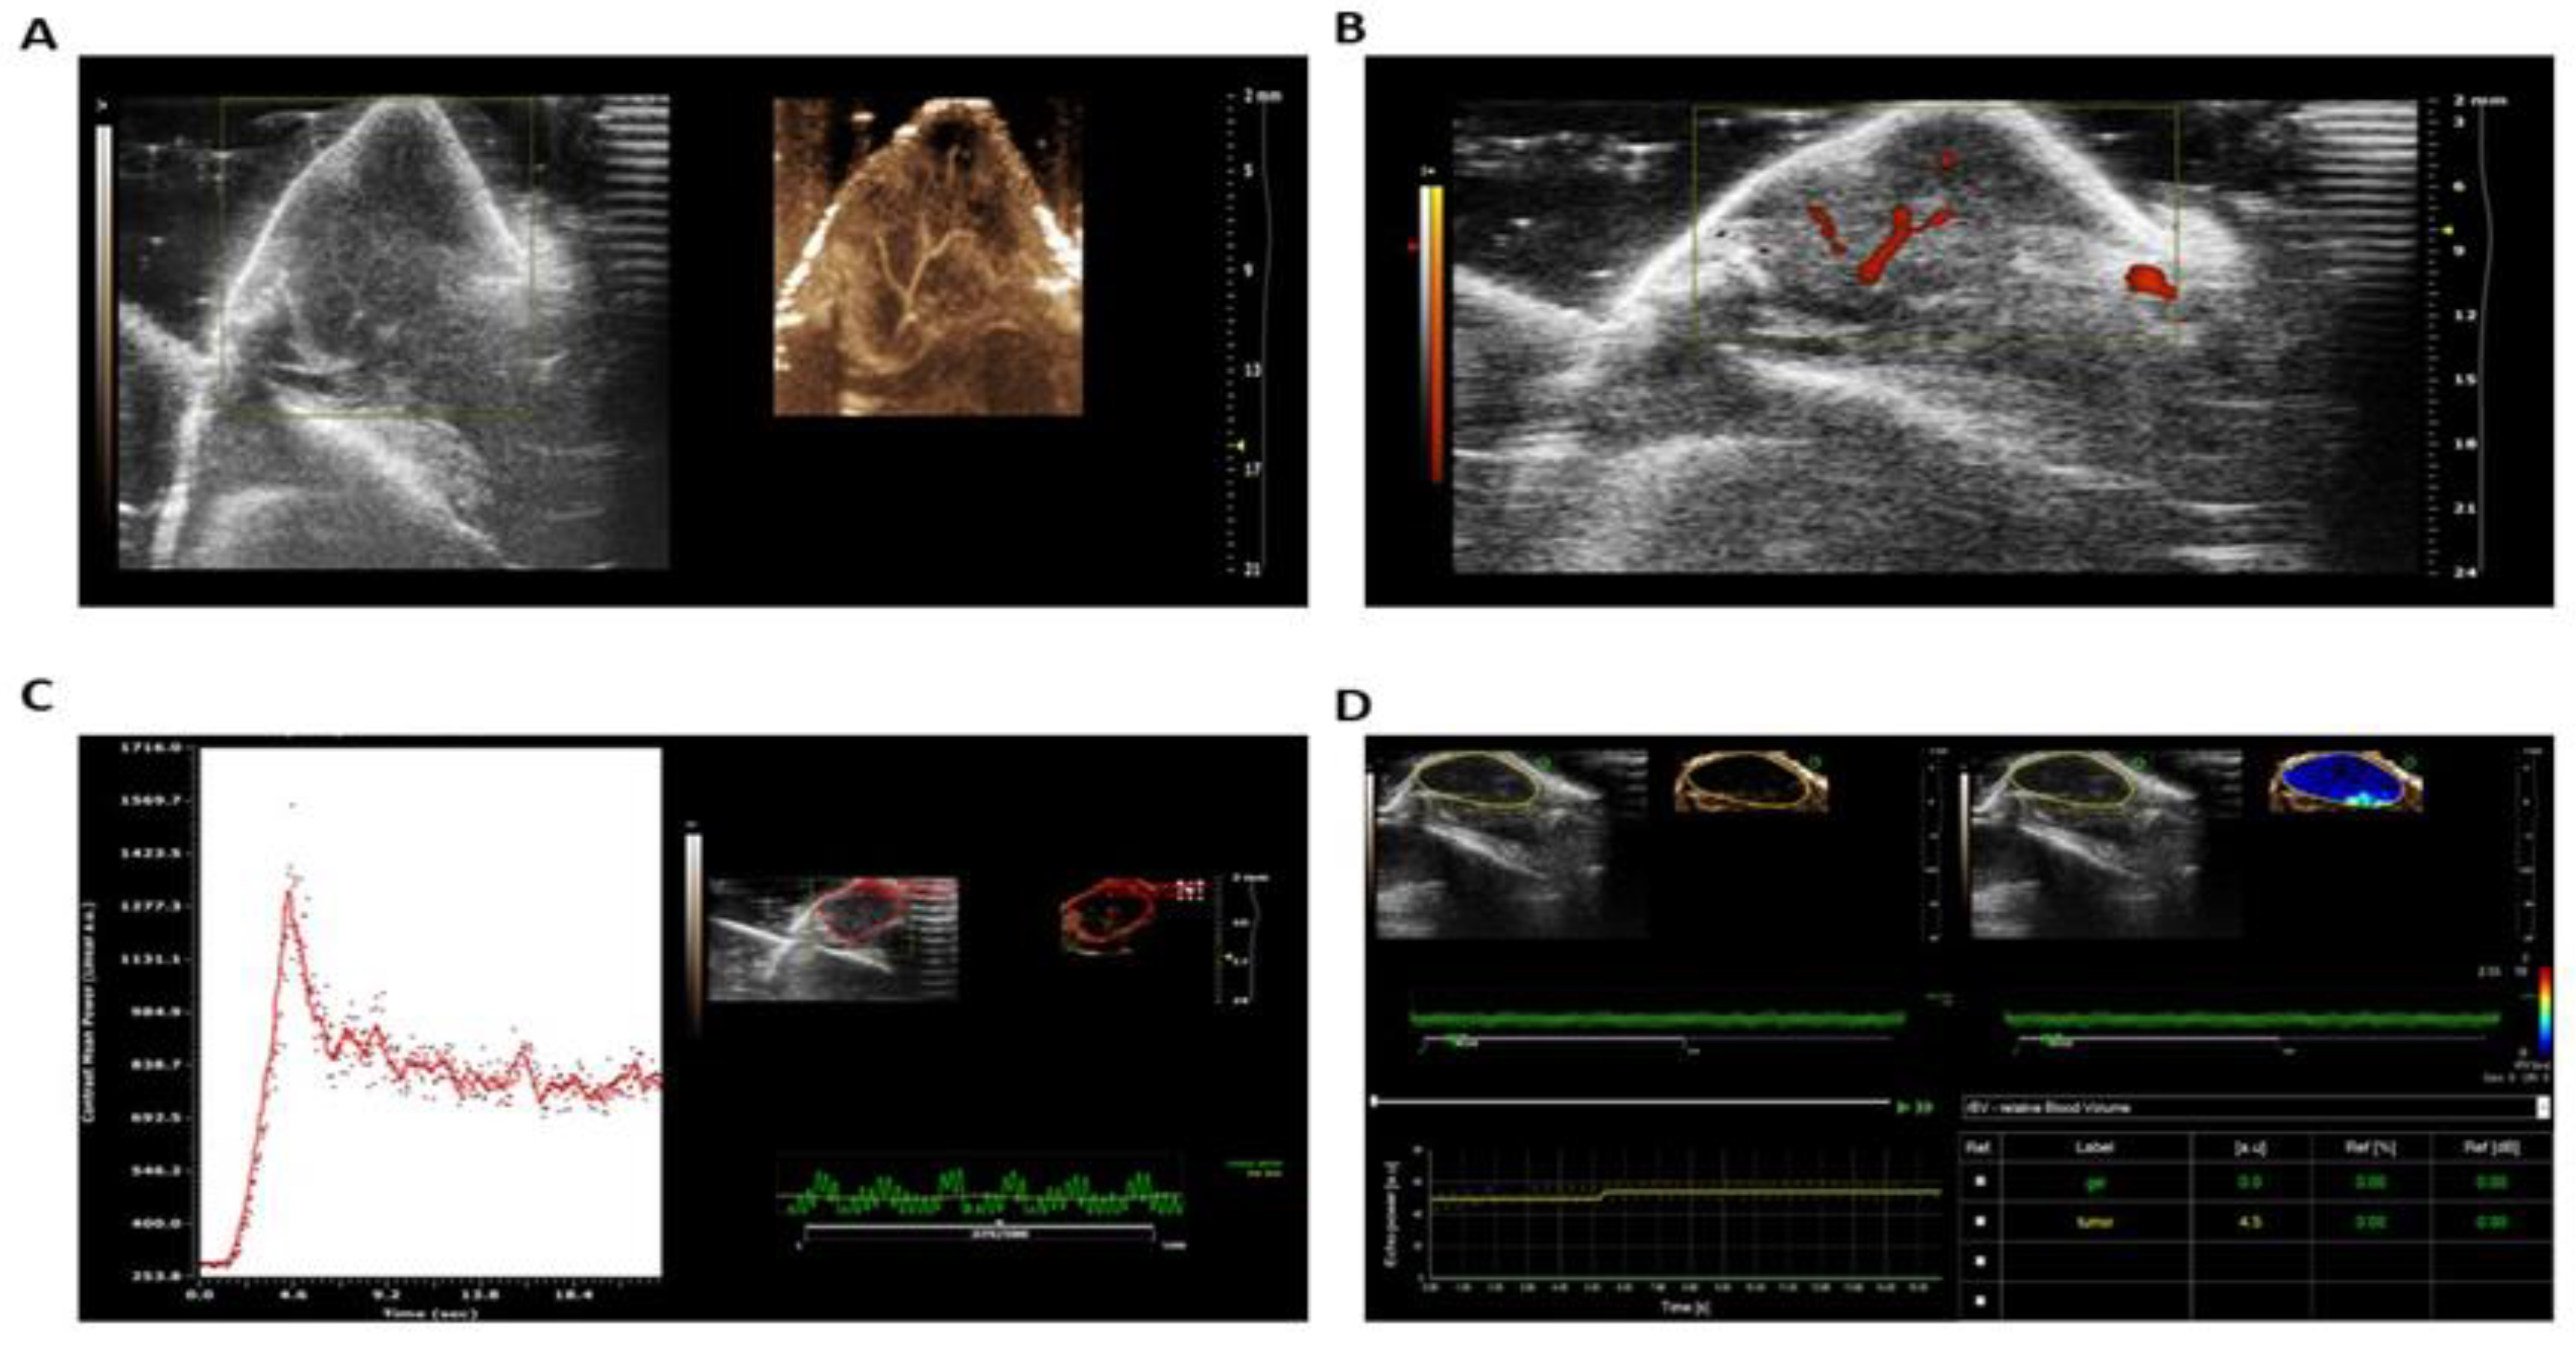

Ultrasound highlighted the comparison of tumor vascular microvessels from B-mode in the left image to non-linear non-targeted contrast with microbubbles, showing clearer definition of tumor vessels including microvessels (Figure 6A). Power Doppler mode was used to visualize large tumor vessels (Figure 6B). Figure 6C shows the visualization and quantification of tumor perfusion. Quantification of relative blood volume was shown using Visualsonics Vevo 2100 Vevo CQ software (Figure 6D). Figure 7 shows a series of images of mice treated with curcumin and EGCG showing complete remission four months after tumor injection as assessed by fluorescence microscopy.

Figure 6. Nonlinear ultrasound with non-targeted contrast imaging of the tumor for visualization of tumor blood flow and perfusion.